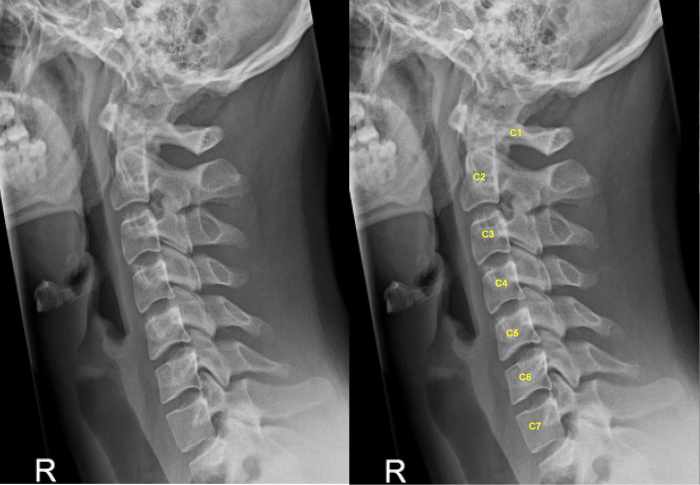

Lateral (from the side) X-ray of the cervical spine showing the number of the vertebrae, C1 to C7.

By Lucien Monfils (Own work) [GFDL (www.gnu.org/copyleft/fdl.html) or CC-BY-SA-3.0-2.5-2.0-1.0 (www.creativecommons.org/licenses/by-sa/3.0)], via Wiki

The vertebrae (backbones)—and the nerves that exit the spinal cord near them—are grouped by location:

- 7 cervical at the top of the neck (designated C1 to C7)

- 12 thoracic from the top to the low back (T1 to T12)

- 5 lumbar in the low back (L1 to L5)

- Then the sacrum and coccyx at the level of the hips and tailbone

The nerves at the origin of the brachial plexus come from the cervical spine, at levels C5, C6, C7 and the first thoracic vertebrae, T1.